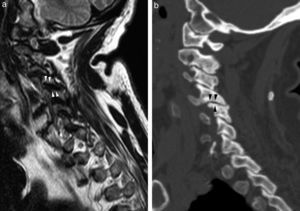

Hiperostosis vertebral idiopáticaLa hiperostosis difusa vertebral idiopática, cuyo acrónimo en inglés es DISH, es una enfermedad caracterizada por la tendencia a la osificación de las inserciones ligamentosas, tendones y fascias con predilección sobre el esqueleto axial, especialmente la columna torácica, pero también frecuente en la columna cervical38–40 (fig. 14).

Hiperostosis idiopática difusa (DISH). Imagen potenciada en T2 (a) y potenciada en T1 (b) en plano sagital donde se visualiza calcificación del LLA(1), LLP (2) y ligamento interespinoso (flecha), así como una importante mielopatía., y tomografía computarizada multidetector de reconstrucción sagital (c).

Es un diagnóstico radiológico definido por los criterios de Resnick y Niwayama (tabla 2, online)40. Típicamente presenta una osificación abigarrada del ligamento vertebral común anterior; sin afectar a su aspecto más posterior, entre el ligamento osificado y el cuerpo vertebral queda como una fina banda radiotransparente. Puede ocasionar compresión de estructuras anteriores, como el esófago, o de los agujeros de conjunción. La osificación puede afectar también al ligamento vertebral común posterior, los ligamentos interespinososo o los ligamentos amarillos. La distribución de la osificación suele ser típica. La osificación del LLA predomina en la columna toracolumbar, mientras que la del LLP predomina en la columna cervical y puede provocar estenosis de canal y mielopatía38,39 (fig. 14).